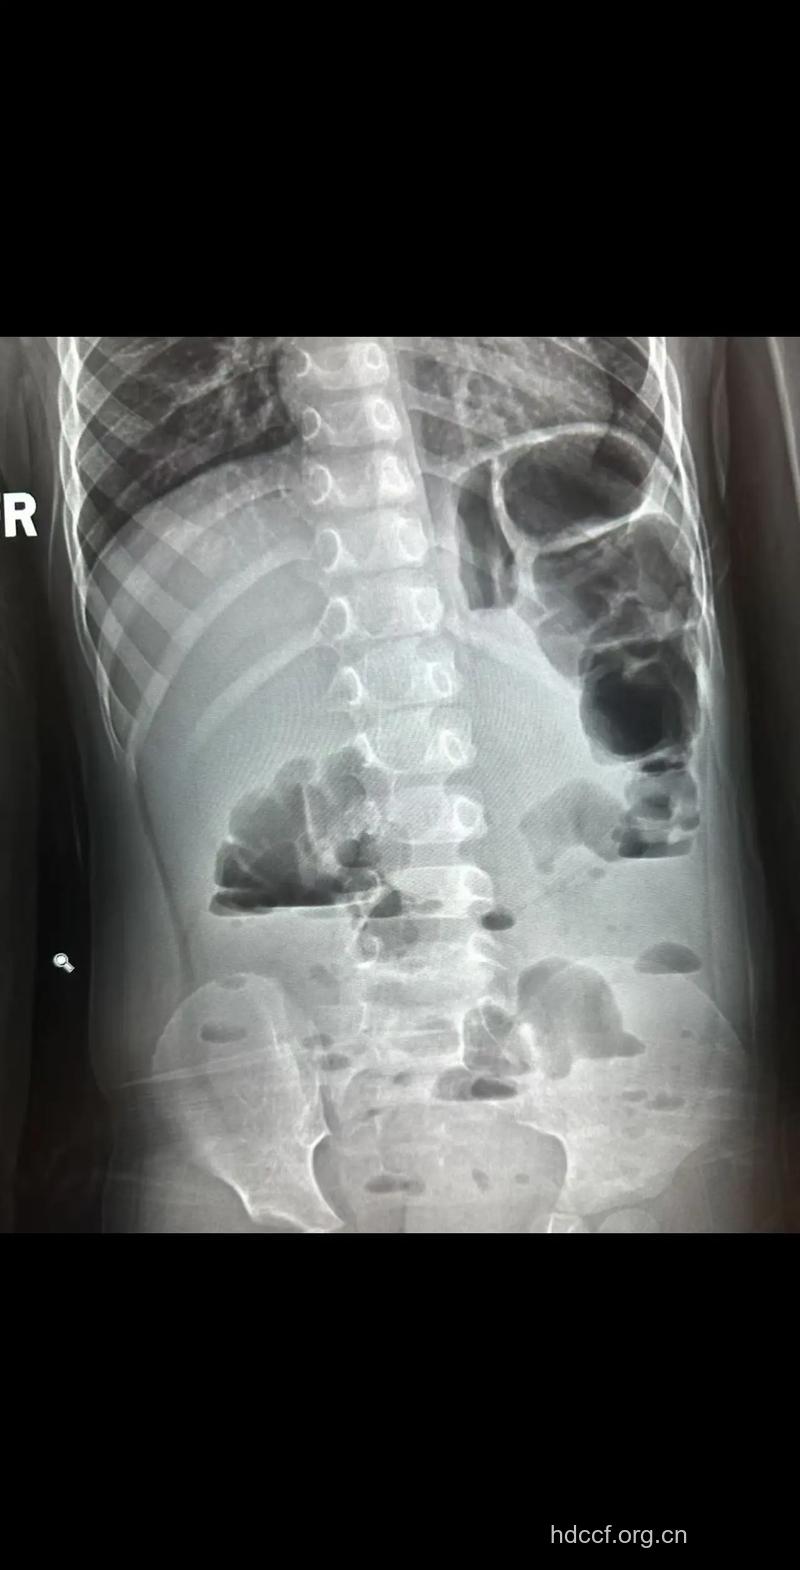

各种原因所致的单纯性结肠梗阻均有梗阻以上肠腔的扩大与积液,扩大的结肠腔以近端结肠(从直肠开始)明显,靠近梗阻点的结肠腔逐渐变小,站立位片可见腹部两侧有较宽大的液平或在盆部见到宽大派平,卧位片扩大的结肠腔内可见火柴头样半月状粘膜皱壁向腔内伸入且不会与对侧肠壁相接,有别于空肠的粘膜皱壁。

有时由于梗阻近端的结肠充气扩大,在气体的衬托下会见到梗阻处肠腔狭窄或软组织样包块影的直接征象。X线可以见到充气扩大的小肠,但扩大程度远较结肠为轻。右半结肠梗阻以积液为主时会误诊为低位小肠梗阻,就算是乙状结肠梗阻,如果以积液为主而缺乏对比时,亦容易造成误诊。此时应再站立透视,转动体位观察肝曲、脾曲有否充气扩大以及充气扩大的肠腔内有否结肠袋不横贯肠腔的皱壁纹,对判断结肠梗阻有重要意义。